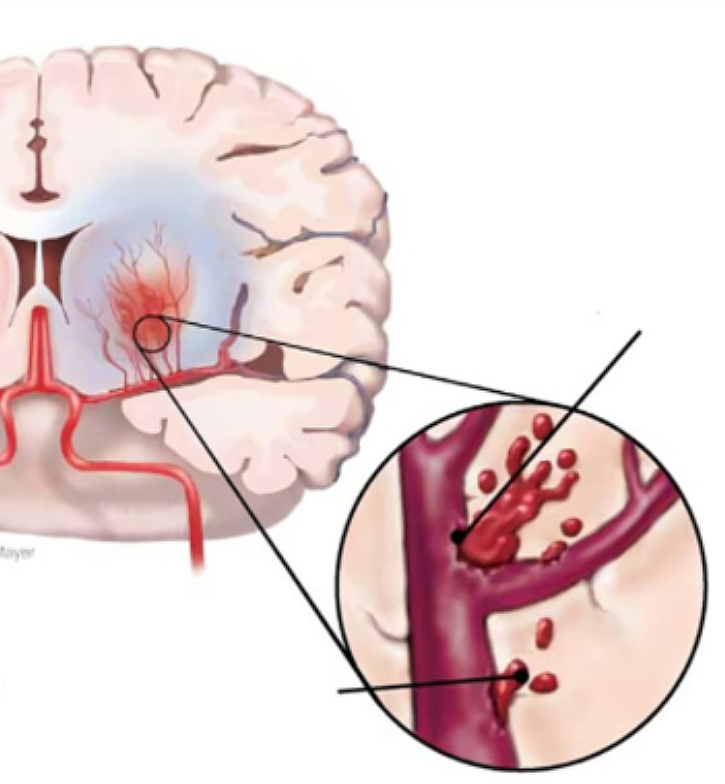

뇌에 혈액을 공급하는 혈관이 막히게 되면 뇌의 일부가 손상되는 ‘뇌경색 증상’, 뇌혈관이 터져 주변 뇌가 손상되는 ‘뇌출혈 증상’이 있습니다. 두 질병 모두 사망에 이르거나 뇌손상으로 인한 후유증이나 신체장애를 남길 수 있는 위험한 질환입니다.

평소에 전혀 그런 일이 없었는데 갑작스럽게 머리에 심한 통증이 생기거나, 메스꺼움과 구토 증세가 나타나면, 뇌동맥이 파열되어서 생기는 지주막하 출혈을 의심해 볼 수 있다. 갑작스러운 두통은 과거에 경험해 본 적이 없는 아주 이상하고 심한 통증을 동반하게 되는데 이런 경우에는 반드시 병원으로 내원해야 합니다.평소와 다른 통증으로 갑자기 머리가 깨질 듯이 아프거나 뒷목에 심각한통증이 느껴진다면 뇌졸중 전조증상으로 보이며 이 증상과 함께 구토가 유발되는 상황이 나타날 수 있습니다.